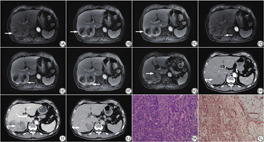

本研究经河北省人民医院伦理委员会批准,免除受试者知情同意,批准文号:2022083。患者男,67岁,主因“发现血糖升高5年,体质量下降4个月”入河北省人民医院。查体:右侧腿部纤维瘤切除术后,右侧大腿根部长约5 cm的手术瘢痕。有慢性乙肝病史5年。实验室检查:AFP 13.880 ng/mL、CA19-9 41.840 U/mL、T-Bil 27.8l mol/L、D-Bil 7.4l mol/L升高。2021年4月27日行MRI(强化应用莫迪司对比剂)示:肝右后叶可见团块状T1WI、T2WI高低混杂信号影,DWI序列呈不均匀高信号影,范围约为101 mm×58 mm,边界欠清,其内可见分隔,T1WI同反相位信号未见明显变化,增强扫描(图1A~1G)呈不均匀强化,内可见片状无强化信号,边缘及分隔强化较明显,肝胆期(延迟1 h扫描)信号不均匀。肝左叶外侧段可见一小圆形异常强化影,直径约8 mm,增强扫描动脉期呈明显强化。门静脉右支可见对比剂充盈缺损影(图1G)。时隔5天后行CT平扫及增强示:肝右叶一类椭圆形略低密度影,增强扫描动脉期呈周边晕状中等强化,间隔强化(图1H),增强扫描门脉期及延迟期病灶由边缘向中心逐渐填充(图1I~1J)。病变边缘可见钙化灶。影像诊断:不典型肝癌可能性大;肝左叶外侧段转移可能。经患者知情同意后于2021年5月8日进行手术,行根治性切除肿瘤。在剖腹手术中,肝脏呈粉红色硬化,肿瘤位于右后肝段。因此,我们进行了右后肝切除加右后门静脉血栓的清除,并在超声引导下的子焦点射频消融。病理上,切除的病灶肉眼观察为多结节型,大小约10 cm×8 cm×6.5 cm。肿瘤切面灰白色、灰红色,质稍硬,局部可见坏死。免疫组织化学染色显示,部分嵌套式生长的上皮细胞表达HepPar-1、CKPAN、精氨酸酶-1,局灶性表达Glypical3,提示为肝细胞癌;而另一部分腺体结构的上皮细胞表达CK7和CK19,不表达精氨酸酶-1和Glypical3,提示为胆管细胞癌。两种上皮成分的波形蛋白均为阴性。肉瘤细胞波形蛋白阳性(图1L),细胞角蛋白7和19、上皮膜抗原和CD34阴性。患者恢复良好,11天后出院。术后行肝动脉化疗和栓塞术。不幸的是手术后仅39天,CT检查发现右肺有早期转移。